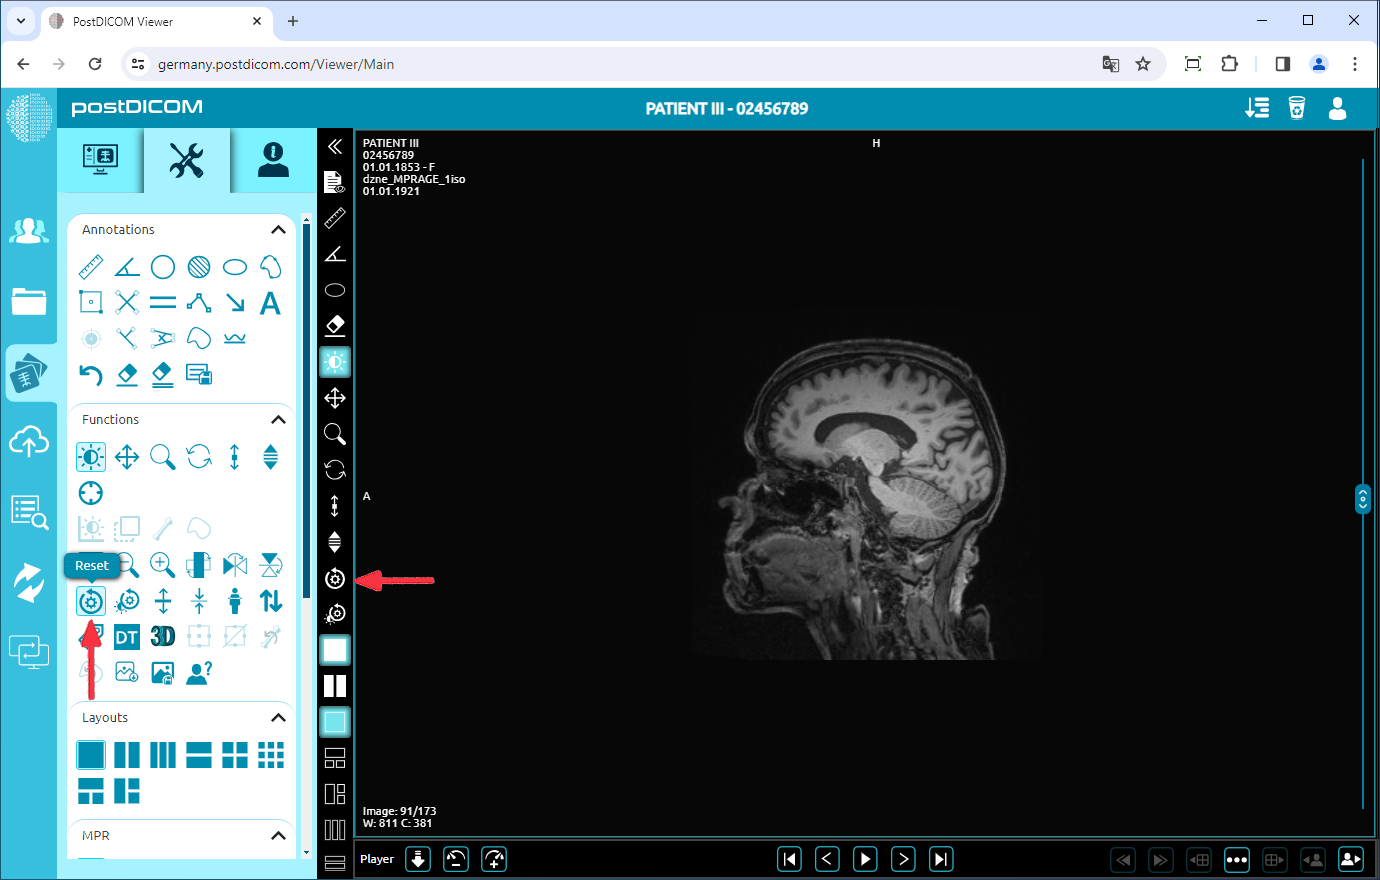

Reset

Click on the “Reset” icon on the left side of the page. After you click on the icon, you will reset all the functions activities on the image and return to the original image.